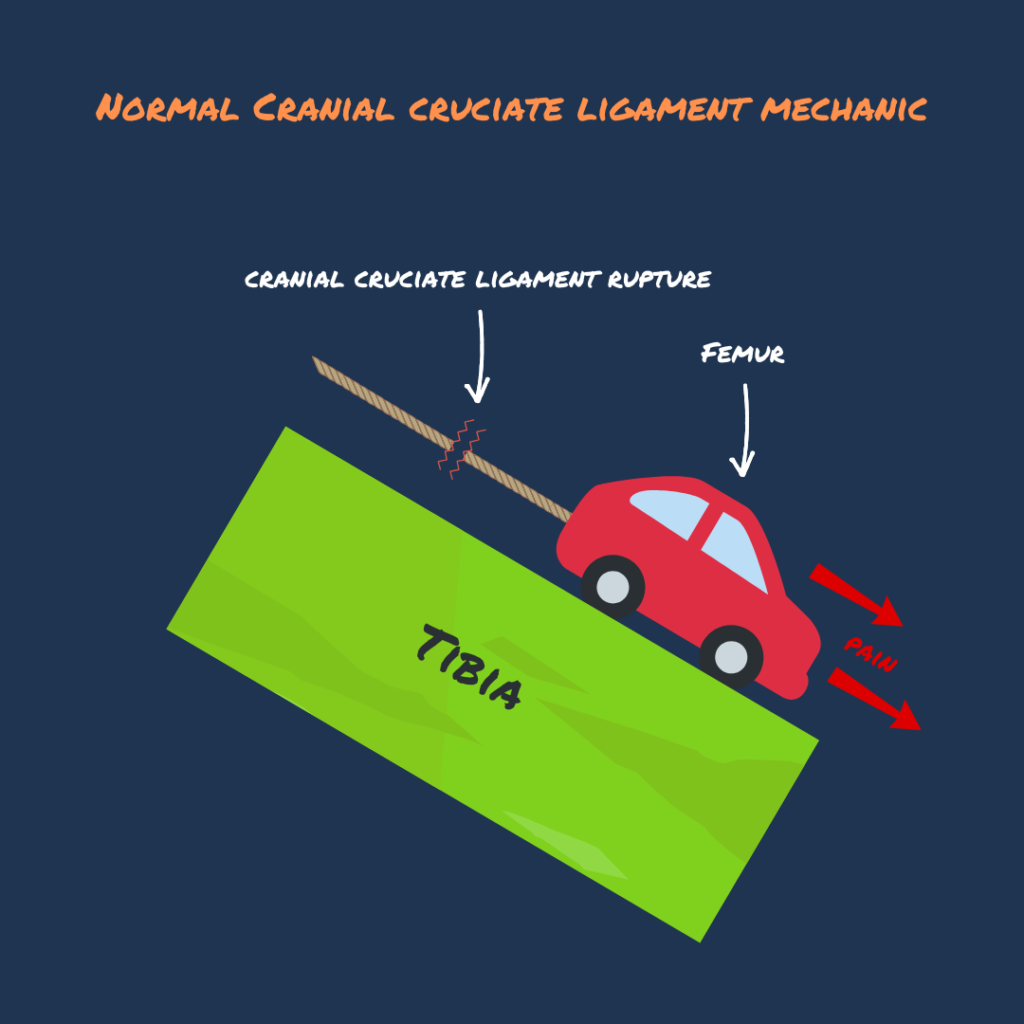

Pic 3 (TPLO): TPLO procedure changes the angle of the slope ⛰ (Tibia), hence there is no need for the rope (cranial cruciate ligament) to hold the red car🚗 (Femur) in place.

The Tibial Plateau Leveling Osteotomy (TPLO) procedure alters the angular relationship between the femur and tibia. The primary goal of this surgery is to reduce forward sliding of the tibia during movement. This is achieved by making a semicircular osteotomy at the proximal aspect of the tibia, rotating the proximal tibial segment, and stabilizing it with a bone plate to facilitate healing. This realignment of the articular surfaces within the stifle joint serves to enhance joint stability throughout the stride cycle and mitigate the development of future joint inflammation and osteoarthritis.